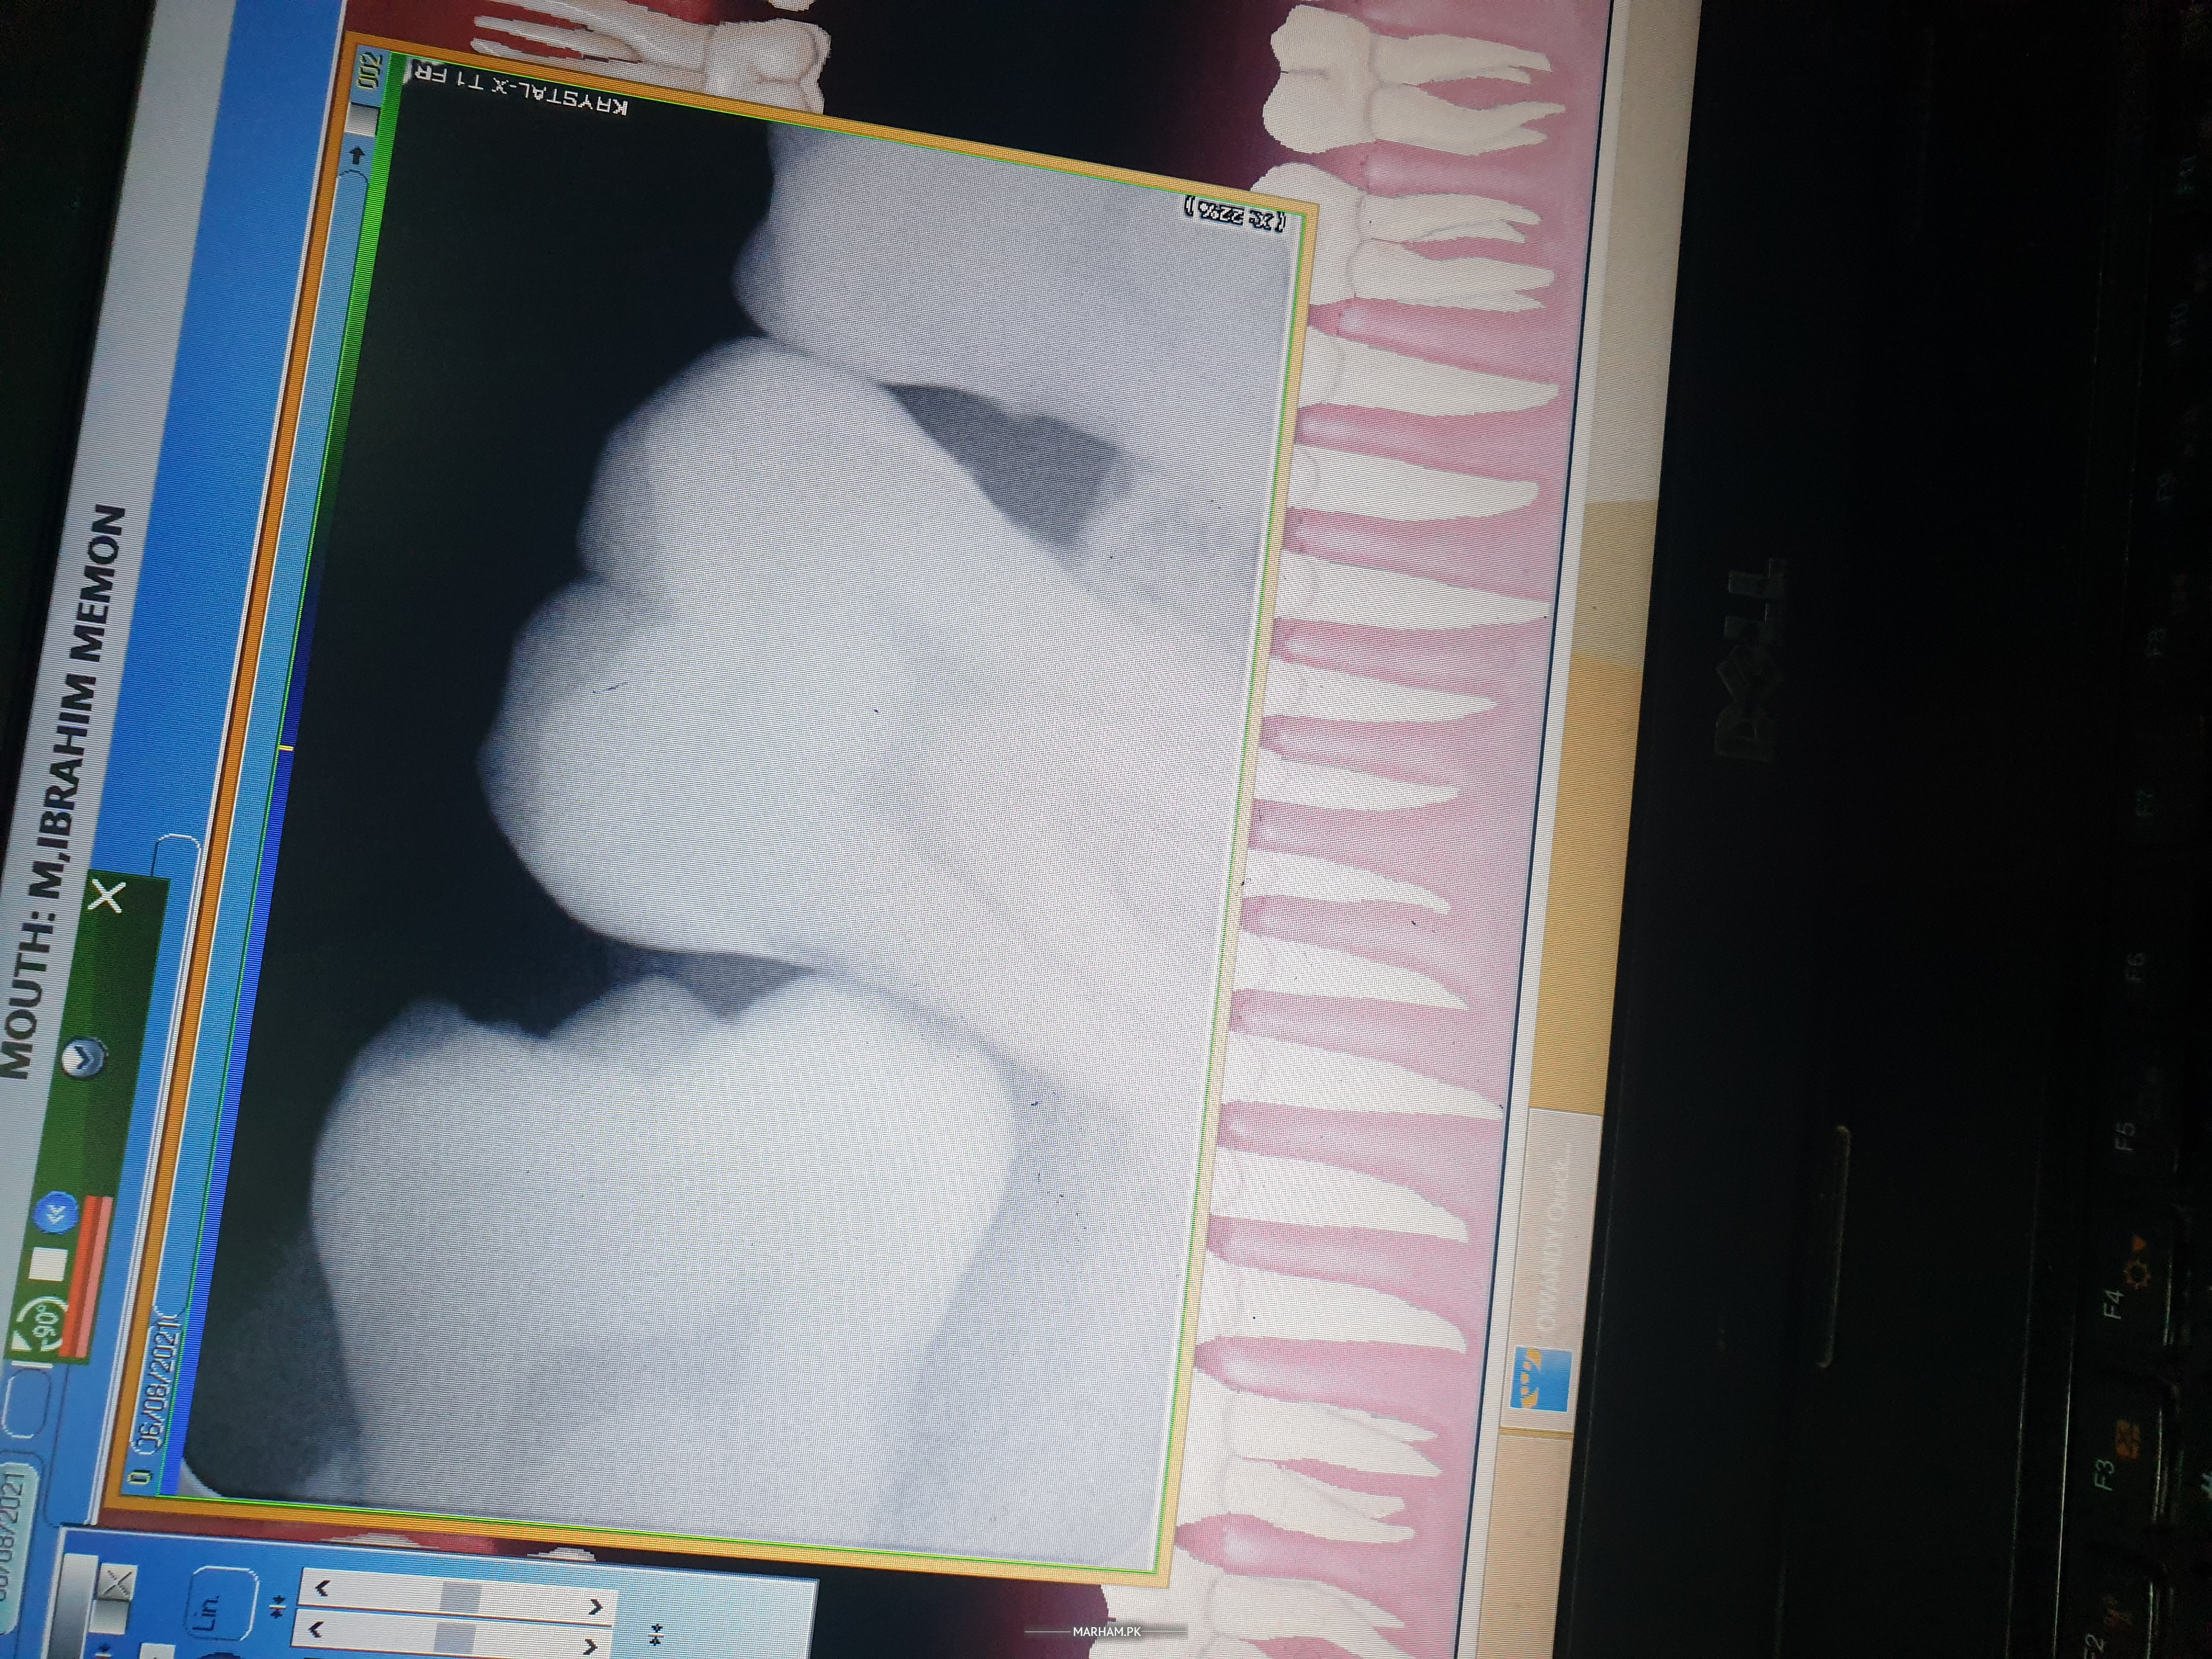

assalam o alaikum doctor kindly ye xray dehk ker treatment bata dain.

Extraction of 3rd molar. and then treatment for second molar

wisdom tooth needs to be removed

n adjacent tooth needs filling

surgical extraction of wisdom tooth and filling of adjacent tooth

Wa slam. Just Xray se treatment decide ni hoti. Clinical condition aur sign and symptoms pe depend krta h. Most probably Lower 3rd Molar impacted h wo 2nd Molar ko bhe damage kr raha h. Apko 3rd Molar ki surgery krwa k remove krwana paray ga Aur may be 2nd Molar ki Root Canal Treatment RCT krwani paray. Jo k clinical sign and symptoms pe depend krta h. Kisi achy Dentist Ko dikhaen.

your wisdom tooth needs to be extracted.

and your 2nd molar tooth will be treated according to your history and sign , symptoms. either RCT or Restoration

Dear patient your wisdom tooth is horizontally erupting that needs extraction. Delay could damage 2nd molar . Please take an appointment with nearby dentist for further assessment and treatment. Thank you

extraction of horizontal impacted third molar and restoration of 2nd molar asap as it is damaging 2nd molar otherwise 2nd will also gone soon

Walaikum asalam apka last tooth is not straight aur woh tera hai and bcz of that the tooth jo uske side mein hain woh damage horha hai . Treatment hai ke last tooth ki extraction hogi means niklega .

extraction of the impacted tooth and most probably RCT of the other affected tooth. this need clinical assessment.

surgical removal of last molar. evaluation of 2nd molar for restoration/ ext

Extraction of wisdom tooth and then treatment for second molar

3rd Molar ( Wisdom tooth) need extraction and then treatment of second molar accordingly.

surgical extraction of third molar and examination of tooth no 7 .

doctors me dosre doctors ke pass extraction ke liye gaya tha unho ne ye xray kiya but is me kuch bhi nahi aya doctor ne kaha sab okay hai.